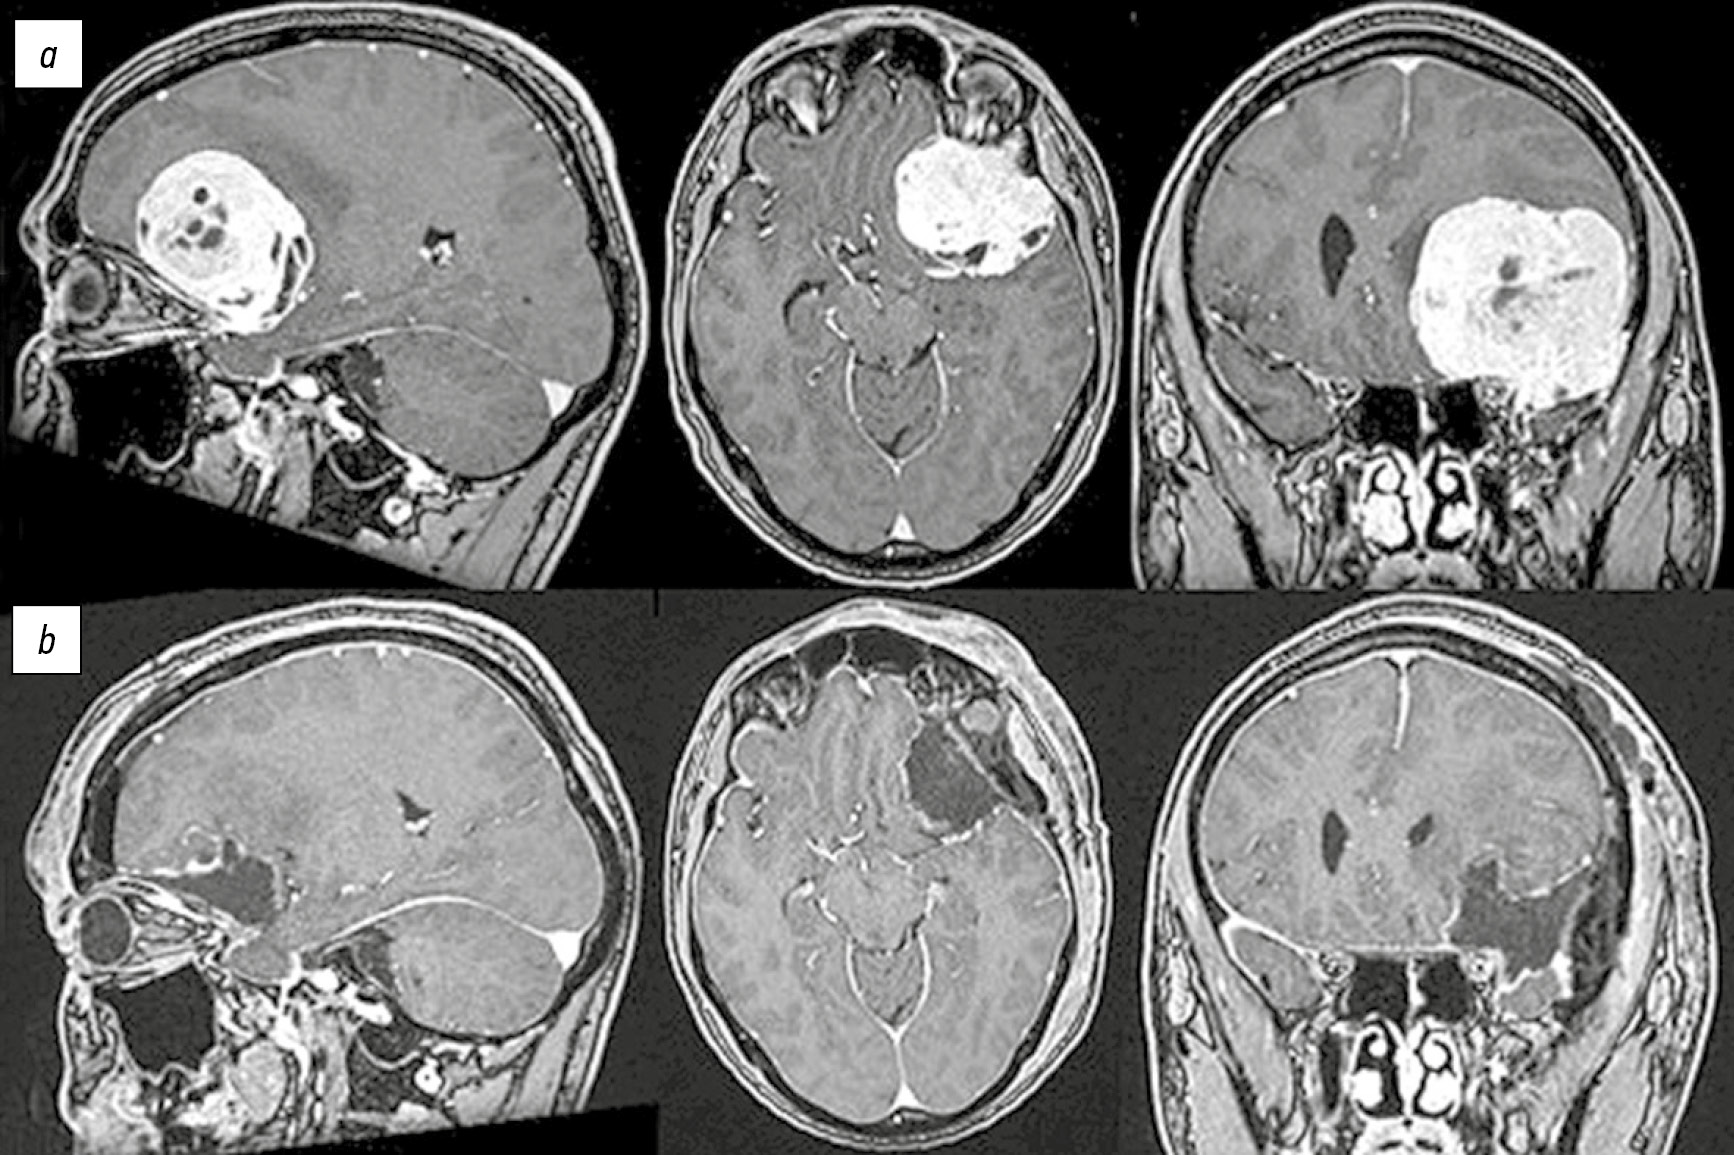

Рис. 1. Данные нейровизуализации пациента с гемангиоперицитомой (Grade 2) в области крыла основной кости слева: a — предоперационная МРТ головного мозга с контрастным усилением, визуализируется гемангиоперицитома с матриксом на большом крыле основной кости слева, размерами 57×42×52 мм, с признаками перифокального отёка, распространяющегося на левую лобную долю; b — послеоперационная МРТ головного мозга с контрастным усилением: патологического накопления контрастного вещества не выявлено, радикальность удаления по Simpson — 3.

Fig. 1. Neurovisualization data of a patient with a Grade 2 hemangiopericytoma in the left wing of the sphenoid bone: a — preoperative MRI of the brain with contrast enhancement, showing a hemangiopericytoma with a matrix on the large wing of the sphenoid bone on the left, measuring 57×42×52 mm, with signs of perifocal edema spreading to the left frontal lobe; b — postoperative MRI of the brain with contrast enhancement: no pathological accumulation of contrast agent was detected, Simpson’s resection grade — 3.